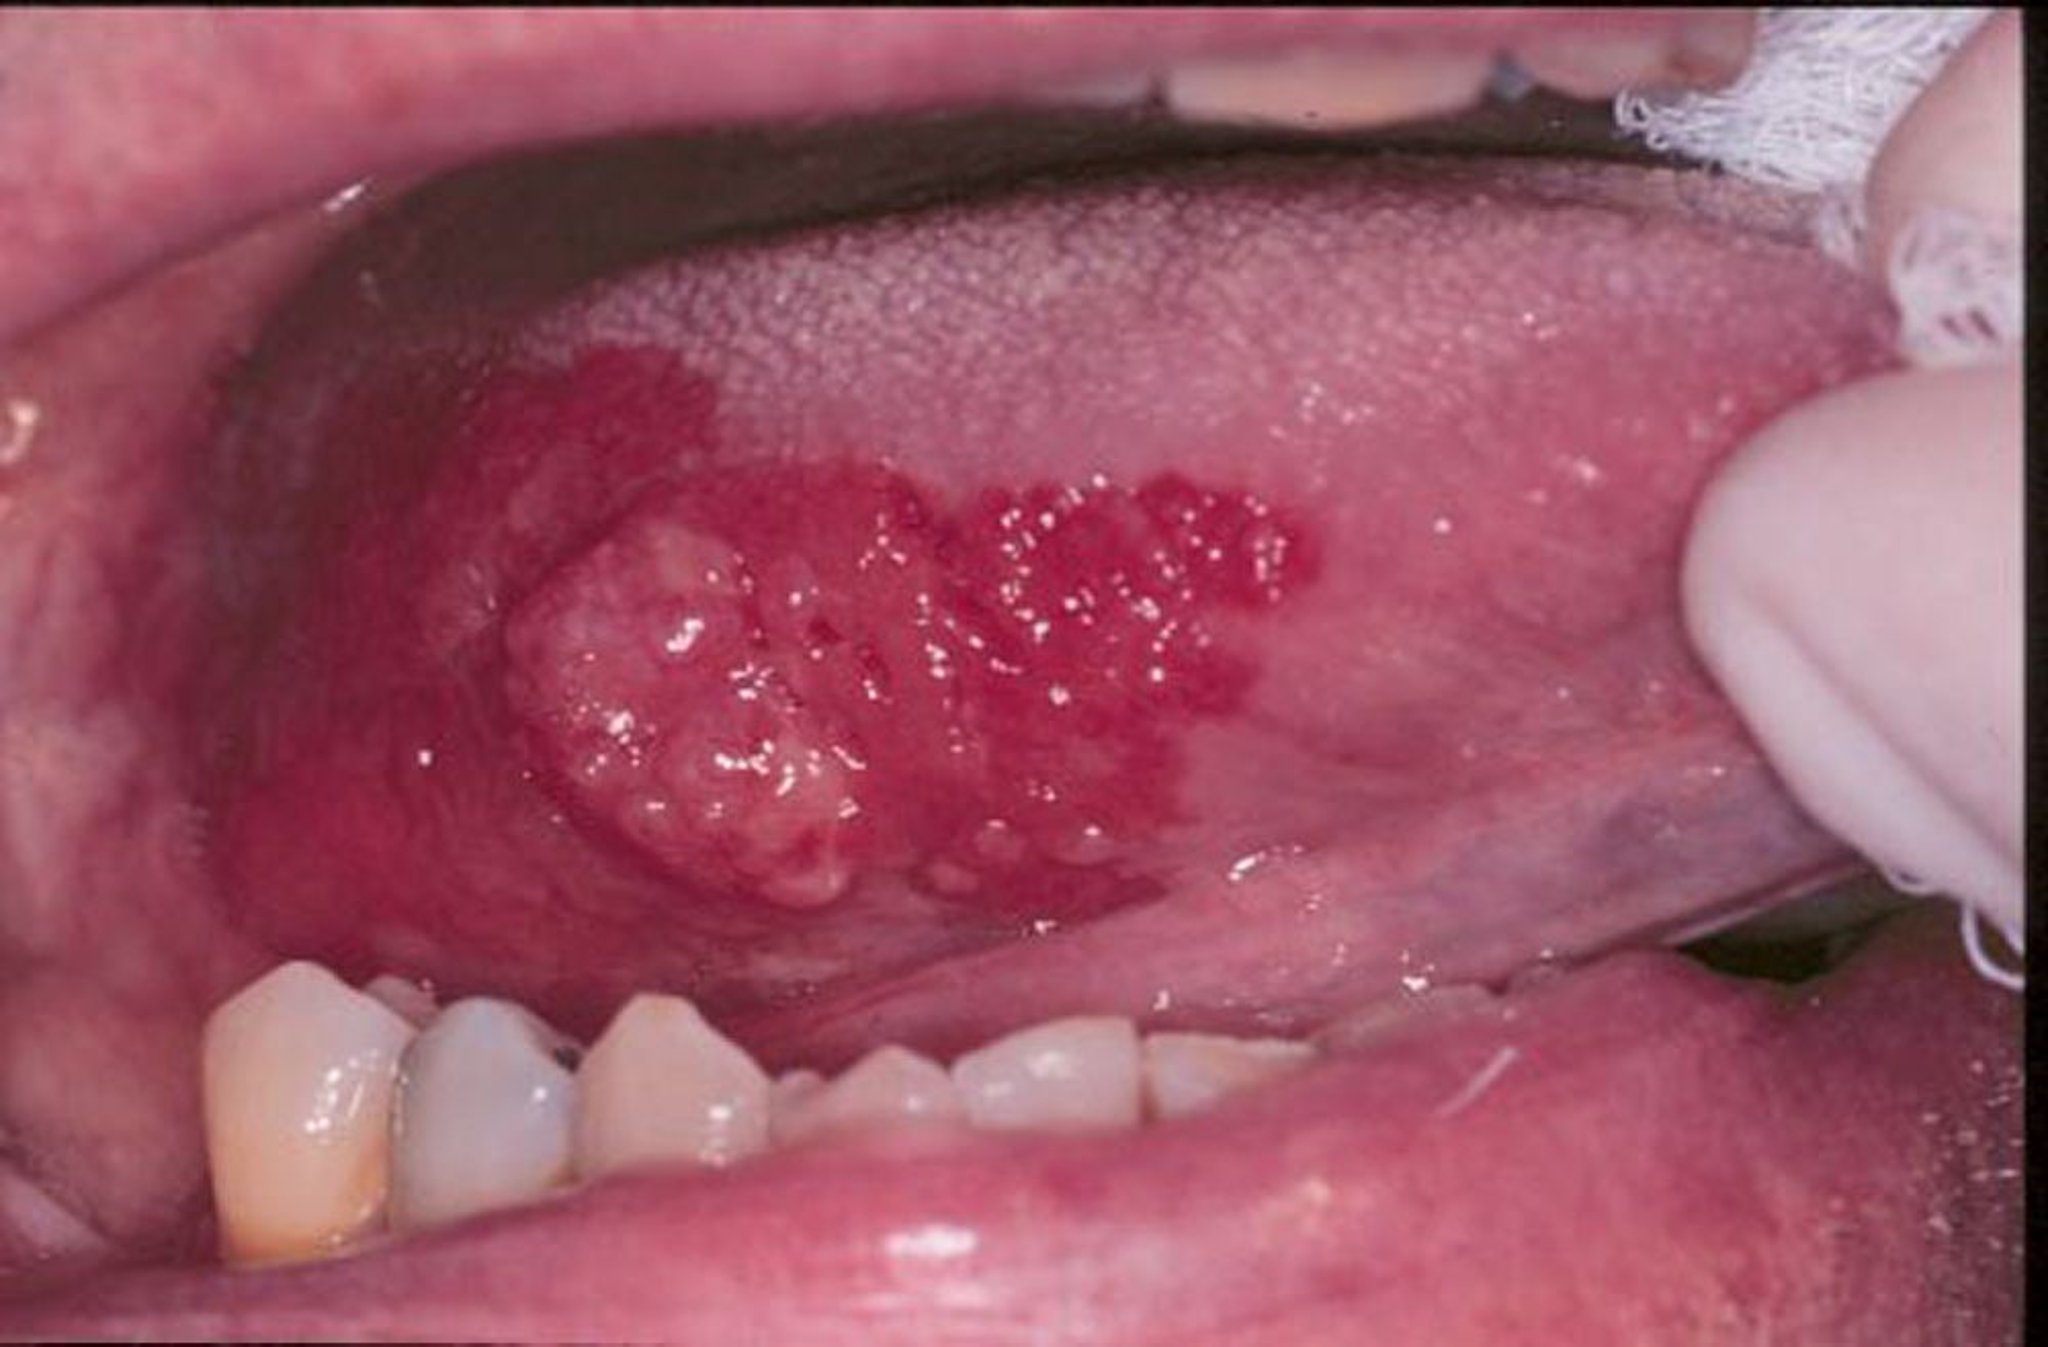

Eritroplachia e carcinoma squamocellulare

L'eritroplachia è un termine generico che può descrivere lesioni morbide di colore rosso, piatte o erose che si sviluppano nella bocca. In questa immagine, un carcinoma esofitico squamocellulare sulla lingua è circondato da un margine di eritroplachia.

Image provided by Jonathan A. Ship, DMD.